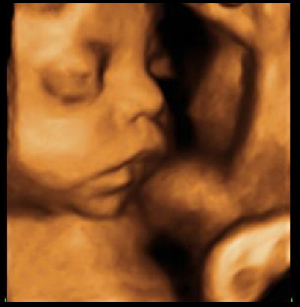

Ecografías en 3D y 4D

¿Has pensado en hacerte en una ecografía en 3D? Ahora es el momento más adecuado. Para que una ecografía en 3D y 4D ofrezca unas buenas imágenes, se requiere que haya una cantidad de líquido amniótico suficiente. Pero además, puesto que lo que buscas con este tipo de ecografías es sobre todo ver al bebé, te gustará que tu hijo presente un buen aspecto.

Si la ecografía se hace muy pronto, tu pequeño no va a dar su mejor instantánea, ya que es a partir del final del segundo trimestre cuando empieza a acumular grasa y a ofrecer ese aspecto de “bebote”. Más tarde de la semana 31 de embarazo, tu hijo es tan grande que apenas tiene sitio para moverse y además apenas hay líquido amniótico, lo que empeora la calidad de las imágenes.